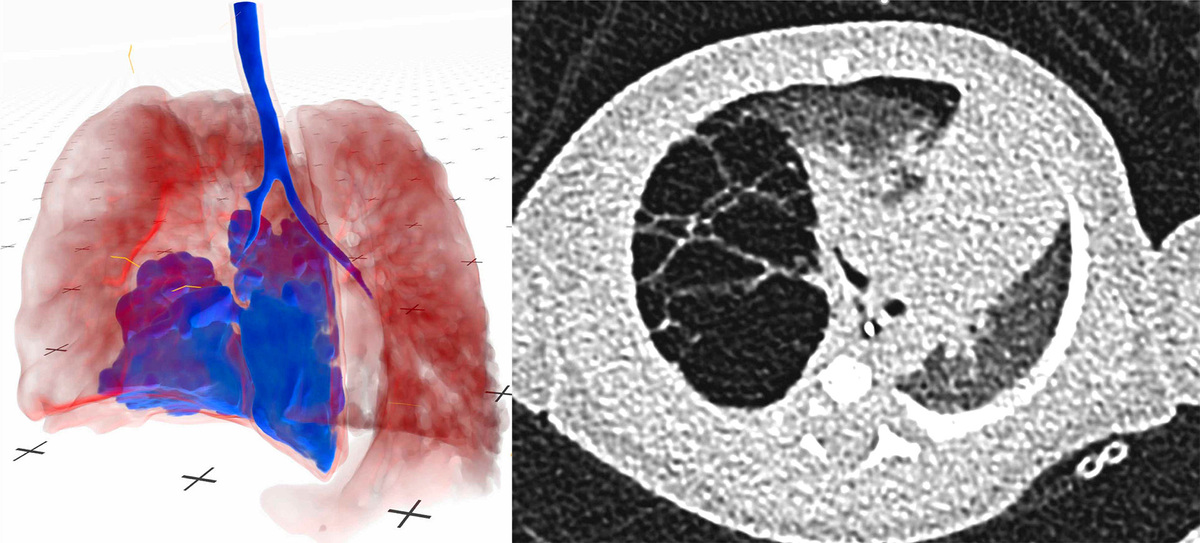

Low-dose CT, high-impact: VR is redefining pediatric surgery